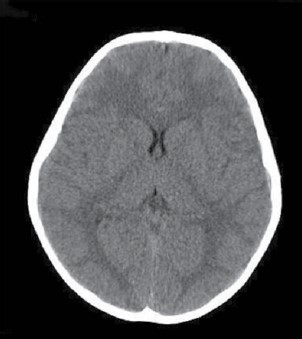

Paciente do sexo feminino com 30 anos de idade, procura serviço de neurologia com queixa de cefaleia há 6 meses, de média intensidade, holocraniana, muito frequente (diária), com piora progressiva, acompanhada de embaçamento visual e episódios de escurecimento da visão. Negou náuseas ou vômitos. Ao exame, a pacientes estava normotensa, afebril, consciente e orientada, sem sinais de localização e edema de papila bilateral na fundoscopia. Referiu 3 meses antes do início dos sintomas ter sofrido trauma crânio encefálico. Apresentou o exame de imagem a seguir. Com esses elementos, assinale a alternativa que apresenta qual seria a sua hipótese diagnóstica.

Paciente com 50 anos de idade, apresentou um quadro súbito de alteração do olhar conjugado vertical para cima, com preservação dos movimentos horizontais, nistagmo, convergência-retração e dissociação luz-perto. A foto ilustrada é mostrada abaixo.

Qual é a região comprometida (topografia da lesão)?